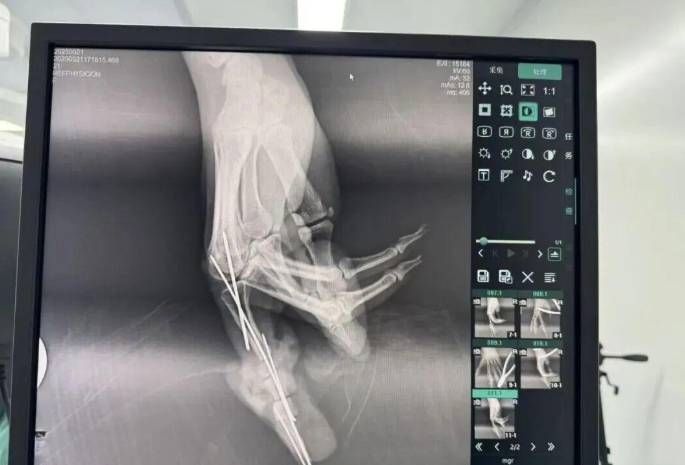

為確保手術(shù)成功,楊志主任特別聯(lián)合劉金海主任組成多手術(shù)組協(xié)作團(tuán)隊,充分發(fā)揮梯隊配合優(yōu)勢,反復(fù)研討后確定了“組合式”手指再造方案:利用右足踇趾的皮瓣、末節(jié)甲床及部分趾骨,聯(lián)合第二趾的趾間關(guān)節(jié),再取部分髂骨進(jìn)行精確植骨,將這些組織精密拼裝,重建一個兼具良好外形和功能的新示指。

多手術(shù)組協(xié)作,40倍顯微鏡下的“精微繡花”

手術(shù)當(dāng)天,多手術(shù)組梯隊配合的優(yōu)勢得到充分體現(xiàn)。無影燈下,楊志主任與團(tuán)隊各司其職、緊密配合,一場漫長的生命接力就此展開。在放大40倍的專業(yè)手術(shù)顯微鏡下,醫(yī)生們開始了精細(xì)操作。楊志主任在術(shù)后解釋道:“患者需要吻合的血管直徑僅0.5-1.0毫米左右,末節(jié)手指的毛細(xì)血管更是細(xì)如發(fā)絲。我們必須將移植組織與手部的血管、神經(jīng)、肌腱進(jìn)行精準(zhǔn)吻合,確保移植組織通血成活。這不僅要求醫(yī)生有扎實的顯微外科技術(shù),還要具備專業(yè)的整形外科審美能力,才能讓再造的指尖既好用又好看?!?/p>